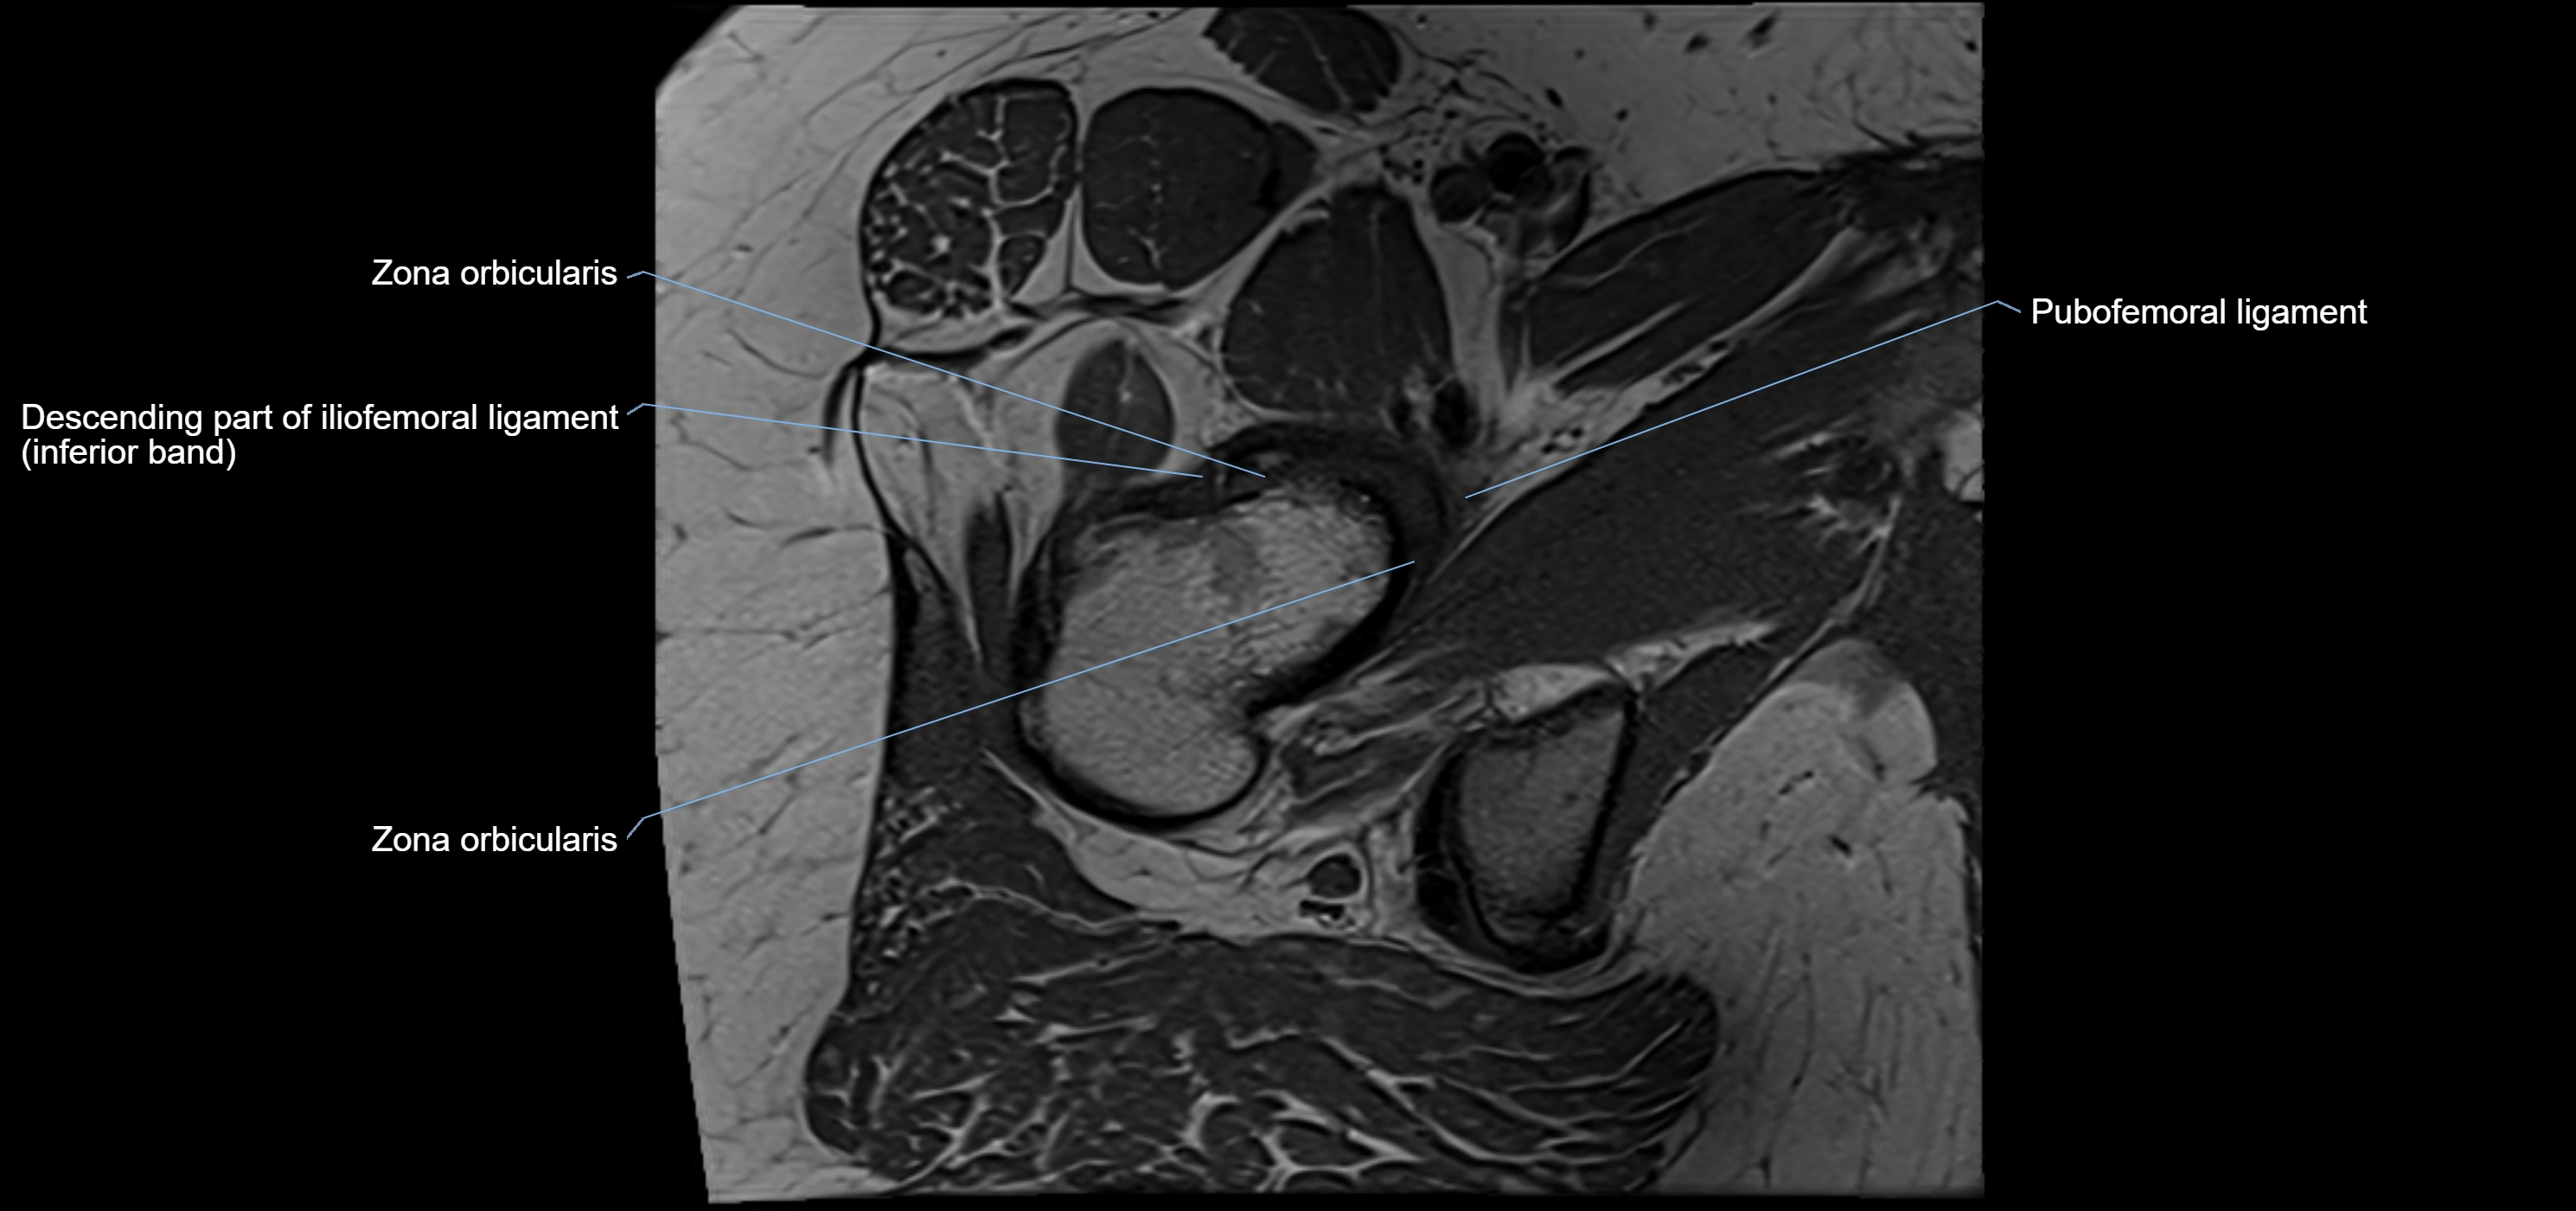

The acetabular labrum is a fibrocartilaginous ring that surrounds the rim of the acetabulum in the hip joint. It deepens the hip socket, increases joint stability, and maintains a suction seal that preserves negative intra-articular pressure. Structurally, the labrum transitions from hyaline cartilage of the acetabulum to dense fibrocartilage at its free edge.

It is triangular in cross-section, with its base attached to the acetabular rim and its apex projecting toward the femoral head. The labrum is most robust superiorly and anteriorly, where load bearing is greatest, and relatively thinner inferiorly.

Structure and Relations

• Superior and anterior labrum: thickest portions, stabilizing against anterior dislocation

• Inferior labrum: blends with the transverse acetabular ligament bridging the acetabular notch

MRI Appearance

T1-weighted images:

• Labrum: low signal intensity (dark)

• Surrounded by intermediate signal joint fluid (bright on arthrogram)

• Tears: linear or focal areas of intermediate-to-high signal interrupting labral continuity

T2-weighted images:

• Joint fluid: bright, making labral tears visible as fluid extending into or around labrum

• Degeneration: may show areas of increased signal within labrum